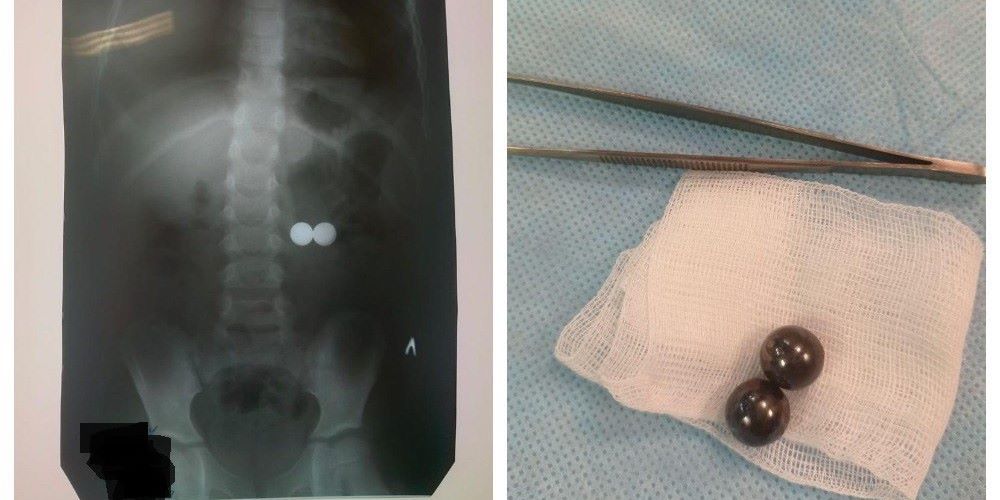

Маленькі магніти у руках дитини можуть призвести до великих трагедій